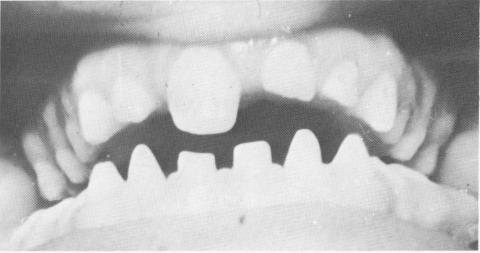

Fig. 15-84. A case of almost complete anodontia of the permanent teeth.

4 Case of almost complete anodontia of permanent teeth, pin consderation